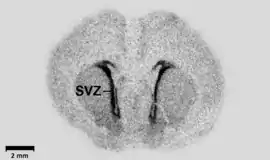

اتورادیوگرافی یک نوع روش تصویر نگاری با استفاده از مواد رادیواکتیو، برای سلولها و بافتها است.

در صورتی که سلولهایی حاوی اتمهای رادیواکتیو بر روی یک لام ثابت شوند و با محلول عکاسی پوشانده شده، در تاریکی برای مدت مناسب نگهداری شوند، در محلهای تشعشع رادیواکتیو، لکههایی بر روی فیلم مشاهده میشود. اگر سلول به وسیله یک ماده دارای فعالیت رادیواکتیو ضعیف، مانند تریتیوم، نشاندار شده باشد، لکه حاصله به اندازه کافی برای تعیین مکان نشاندارشدن در سلول، کوچک خواهد بود. در روش اتورادیوگرافی، با استفاده از تیمیدین نشاندار شده با تریتیوم به عنوان یک نشانگر اختصاصی، میتوان تکثیر DNA را مورد بررسی قرار داد. یک نوع تغییر یافته از این روش که از پروبهای اسید نوکلئیک نشاندارشده استفاده میکند، دورگه سازی در جا نامیده میشود که برای شناسایی وجود اسید نوکلئیک ویروسی، باکتریال و قارچی در سلولها و بافتها بکار میرود.